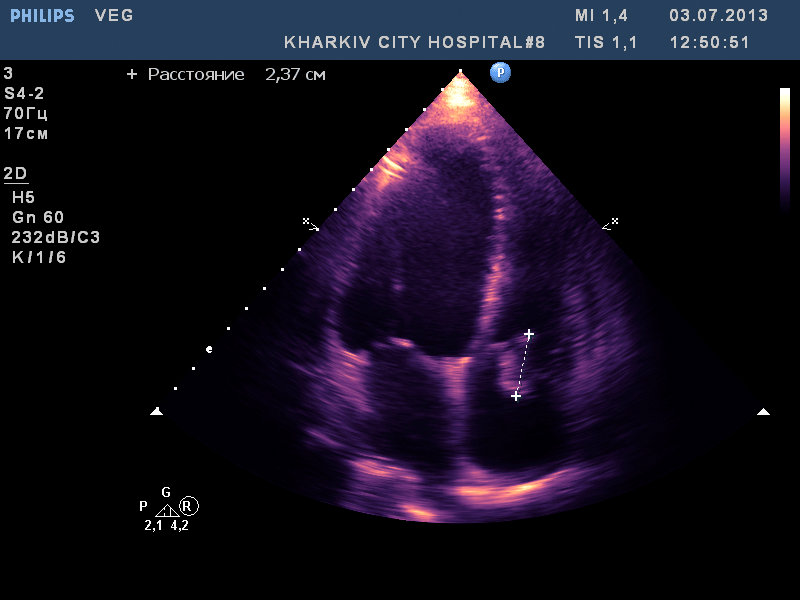

вегетации на АК, МК и ТК

:shock: вегетации на АК, МК и ТК,дилатация полостей, выраженная недостаточность клапанов.

молодой 37лет, с гепатитом C, возможно имеет место быть ВИЧ. по виду наркоман с конкретным стажем